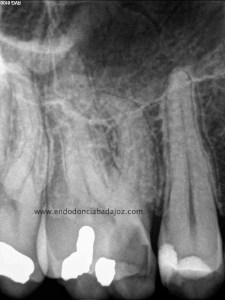

Primeros molares superiores con 3 conductos mesiales

Como todos sabemos, encontrarnos dos conductos en la raíz mesiovestibular de un primer molar superior, cada vez es más frecuente, no por que antes no existiesen, sino por que cada vez somos más conscientes de su existencia,de la anatomía del sistema de conductos tan complicada que puede alojarse en esta raíz, con lo que buscamos ese cuarto conducto. Partamos de la base , que si los buscamos podremos localizarlos, pero hay veces que la cosa se pone algo más complicado, cuando, podemos apreciar un conducto más, quizás se trate de un istmo prolongado del cuarto conducto, pero que en cualquier caso debemos desbridar , limpiar y obturar, con lo que debemos tratarlo como otro conducto.

(un molar superior con tres conductos mesiales)